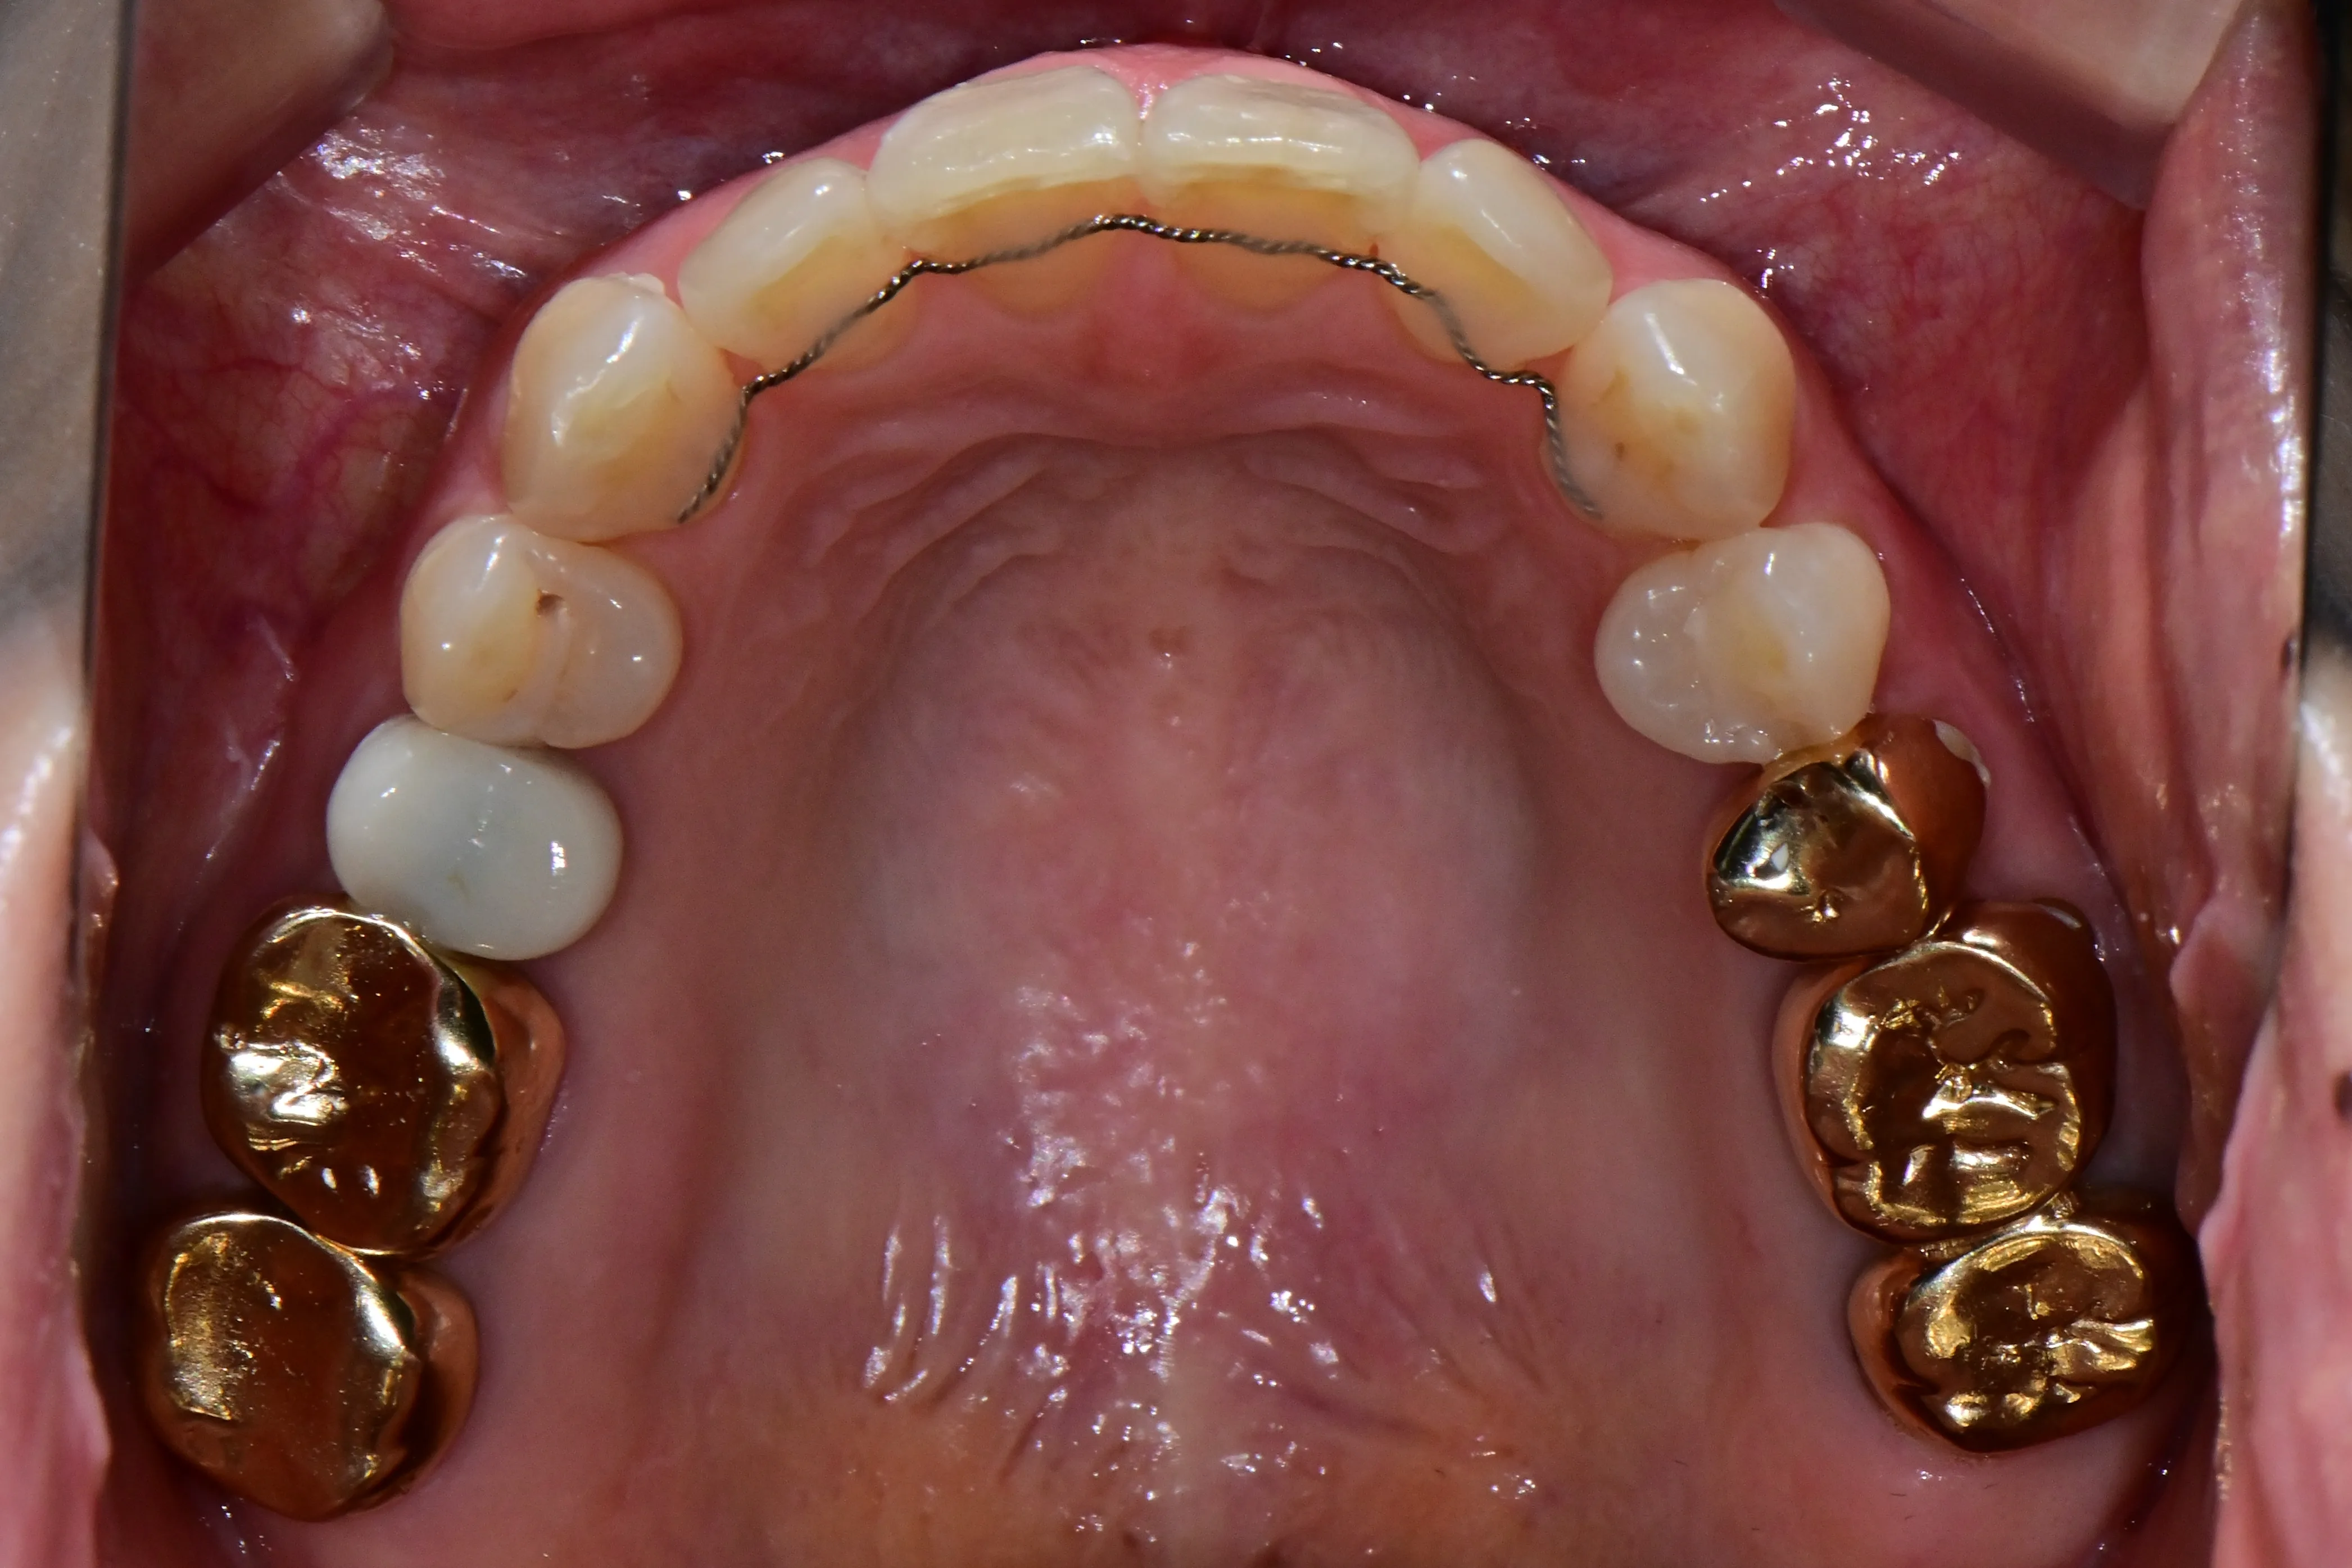

이 환자분은 이미 구강 안에 여러 개의 임플란트와 브릿지 보철물이 있는 상태였습니다. 앞니는 가지런하지 않고, 윗니가 아랫니를 깊게 덮는 과개교합(deepbite)도 있었습니다. 이런 경우 가장 중요한 것은 기존 임플란트와 보철물의 교합을 그대로 유지하면서, 나머지 치아만 가지런하게 배열하는 것입니다.

인비절라인의 디지털 치료 계획을 활용해서, 임플란트와 보철물이 있는 어금니는 움직이지 않도록 고정하고 앞니 위주로만 이동시켰습니다. 덕분에 발치 없이, 고무줄이나 미니스크류 같은 추가 장치 없이도 15개월 만에 치료를 마무리할 수 있었습니다.